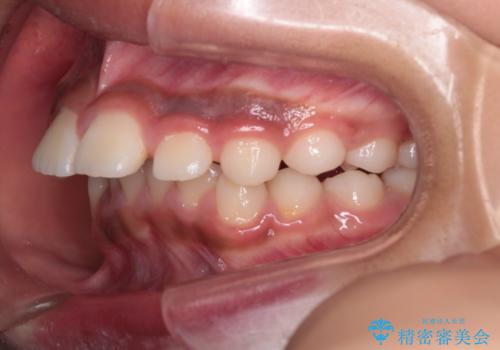

- 患者様は前歯の突出を主訴に来院されました。診査の結果、上顎の前歯が前方に傾斜しており、口元がやや突出して見える状態でした。一般的にこのようなケースでは抜歯矯正が選択肢となりますが、**患者様が抜歯を希望されなかったため、非抜歯での遠心移動(奥へ動かす治療)を計画しました。そのため、リンガルアーチ(歯の裏側に装着する装置)とTAD(歯科矯正用アンカースクリュー)**を併用し、上顎の歯を後方へ移動させながら噛み合わせを整える方法を選択しました。